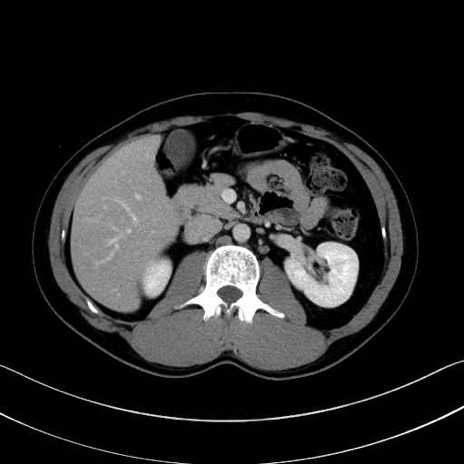

脾静脈の画像解剖

■起始:脾門で脾静脈枝が合流して本幹を形成。

■走行:膵体尾部の後面溝を右走し、膵頸部の後方で上腸間膜静脈(SMV)と合流して門脈を形成。

■主な流入枝:短胃静脈・左胃大網静脈・膵静脈、そして下腸間膜静脈(IMV)(変異あり)。